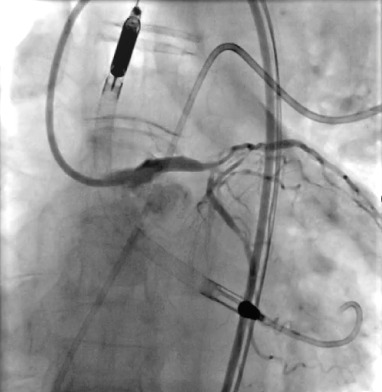

Enter the Impella – a tiny mechanical pump (thinner than a pencil!) inserted through the leg that travels to the heart. Think of it as a backup generator that keeps your house running while electricians fix the main power system.

With Impella supporting his heart, we performed BOTH procedures in ONE session: